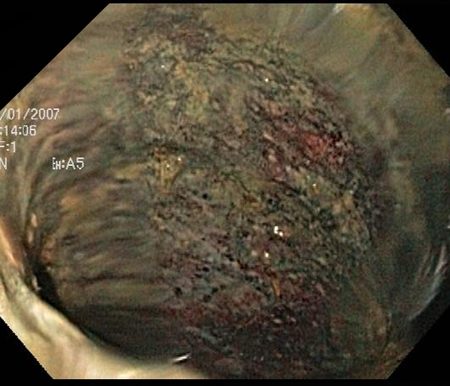

Sigmoidoscopia ou colonoscopia

A sigmoidoscopia ou colonoscopia podem ser usadas para estabelecer o diagnóstico de isquemia colônica, determinar a gravidade e descartar causas alternativas da inflamação colônica. No entanto, se for necessária uma intervenção cirúrgica urgente devido ao quadro clínico do paciente, a cirurgia não deve ser adiada para se realizar uma sigmoidoscopia ou colonoscopia.

[Figure caption and citation for the preceding image starts]: Colonoscopia: demarcação entre cólon isquêmico e normalDo acervo da Dra. Jennifer Holder-Murray; usado com permissão [Citation ends].

[Figure caption and citation for the preceding image starts]: Colonoscopia: denudação da mucosa colônicaDo acervo da Dra. Jennifer Holder-Murray; usado com permissão [Citation ends].

[Figure caption and citation for the preceding image starts]: Colonoscopia: descamação da mucosa e cólon provavelmente não viávelDo acervo da Dra. Jennifer Holder-Murray; usado com permissão [Citation ends].